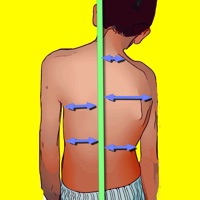

1. -By marking few points at the image of X-ray, the App calculates and offers a very convenient way to determine the most accurate possibly way at once, Pelvic incidence (PI), Sacral slope (SS), Pelvic Tilt (PT), Lumbar lordosis (LL), thoracic kyphosis, PI–LL Pelvic incidence Angle (PI) minus Lumbar lordosis Angle (LL) PI–LL, theoretical normal pelvic tilt (tPT),theoretical normal L1-S1 lumbar lordosis (tL1S1), Pelvic Radius Angle (PRA).

2. Radiographic parameters to evaluate objectively the spinopelvic sagittal balance are Pelvic incidence (PI), Sacral slope (SS), Pelvic Tilt (PT), Lumbar lordosis (LL).

3. -The app offers theoretical value estimation this is particularly useful because a sensible difference between theoretical value and measured value reveals a compensation phenomenon if the pelvis tilt (PT) is higher than its theoretical value, then it is due to pelvis retroversion, which is a compensation phenomenon.

4. Knowing the theoretical value of Pelvis Tilt (PT) provided it is easy to understand that a sensible difference between theoretical value and measured value is a compensation phenomenon.

5. Drawings in patients X-rays and precise measurements are important in order to quantify the magnitude of spinal deformities, to monitor the success or failure of treatment and thus optimise the management of patients according to the severity of the imbalance or even to identify patient at risk of degenerative spondylolisthesis or disk herniation.

11. According to measured parameters the app categorises the severity of the imbalance of spine, in different stages: optimal or non optimal.